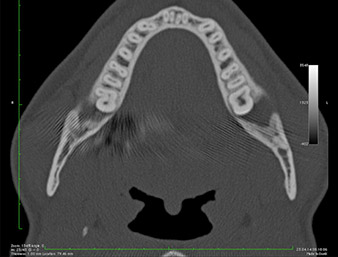

Ya en la ortopantomografía, se constató que había un resto radicular de la región 38 muy cerca del nervio alveolar inferior (figura 1). La raíz se había fracturado durante la osteotomía, pero el primer odontólogo que había tratado al paciente no había extraído esta debido a la presencia de dolor durante la operación.

En la imagen en 3D (tomografía volumétrica digital) se constató que el resto radicular se encontraba muy desplazado en sentido distocaudal en la transición situada entre la porción horizontal y la ascendente del maxilar inferior (figura 2).